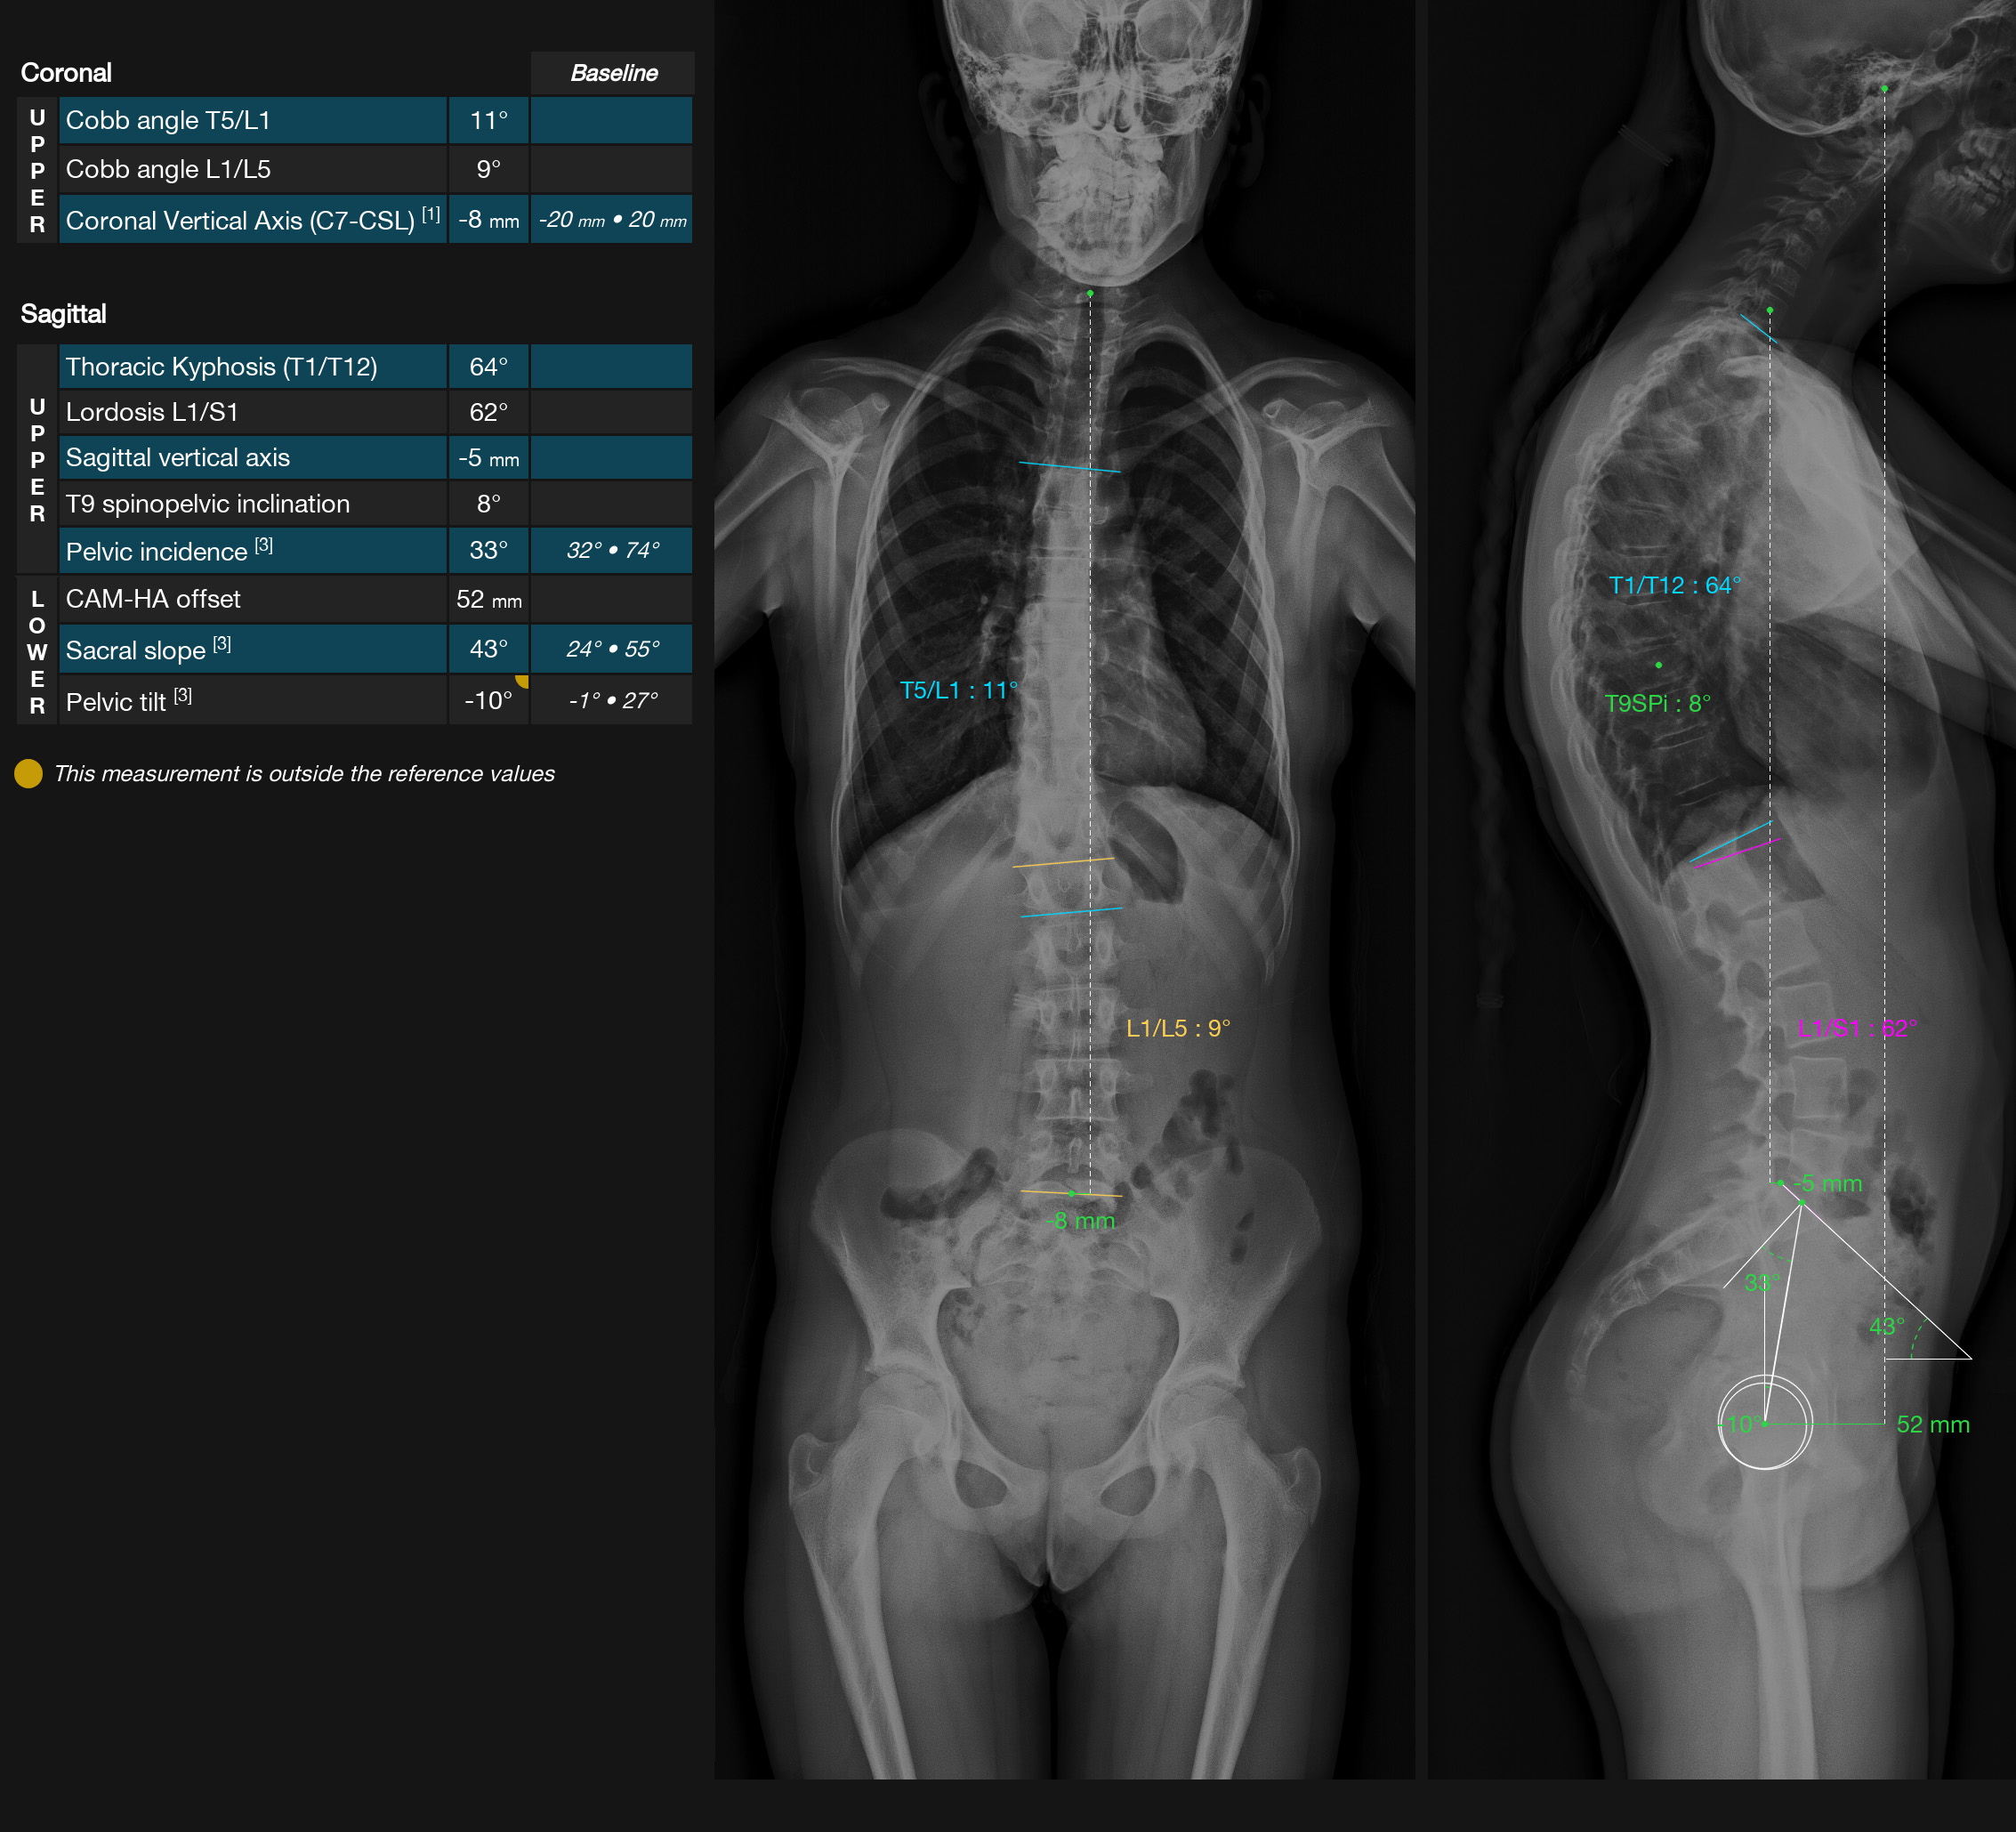

EOS-compatible measurements, with analysis report

TechCare Spine addresses the unique challenge of spinal medical imaging. The spine has significant anatomical complexity, and its central role in body posture and mobility must be leveraged by the latest deep learning advancements. This is why we provide radiologists and orthopedic surgeons with TechCare Spine, a tool for automatic measurements adapted to EOS imaging, offering significant time and productivity savings.

PELVIS : Pelvic version | Pelvic incidence | Sacral slope

SPINE : Coronal balance (CVA) | Sagittal balance (SVA) | Cyphosis T1-T12 | Heel T9 | Lordosis L1/S2 | Cobb angle | Gravity axis

INTUITIVES OUTPUTS showing frontal and profile views together